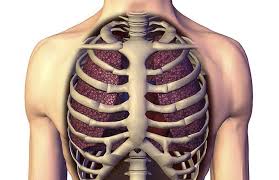

갈비뼈 금간 상태는 외부 충격이나 반복적인 압박으로 인해 뼈에 미세한 균열이 생긴 것을 말합니다. 단순 타박상과 달리 통증이 심하고 숨을 쉴 때, 기침을 할 때 더 크게 아파 일상생활에 불편을 줍니다. 방치할 경우 골절로 진행되거나 폐 손상 같은 합병증으로 이어질 수 있어 주의가 필요합니다.

따라서 증상 인지부터 정확한 진단과 치료까지 체계적인 관리가 필수입니다. 이번 글에서는 갈비뼈 금간 증상, 진단 방법, 치료법을 자세히 정리했습니다. 아래 요약표로 쉽게 확인해보세요!